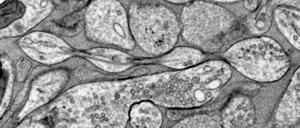

Welche Eiweiß-Ablagerungen im Gehirn führen wirklich zur Demenz? Durch ein besonderes Experiment haben Forschende mehr darüber herausgefunden. Doch wie viel hilft das in der Praxis?